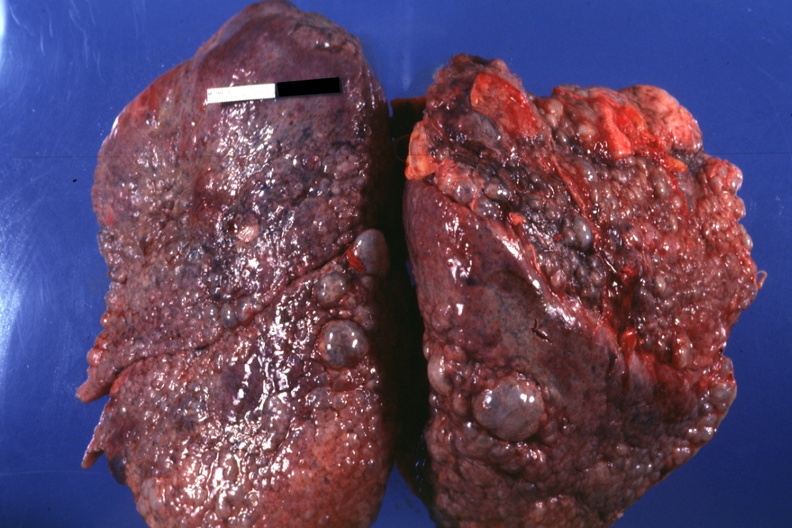

_左下肺肺纖維化病灶

_原發性肺纖維化晚期

_重度肺纖維化的晚期

_重度肺纖維化晚期症狀